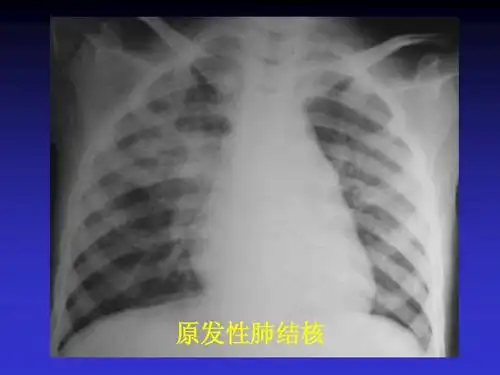

原发性肺结核